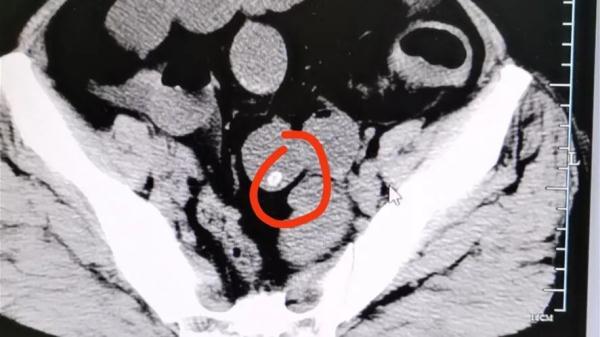

经CT检查后发现胃潴留,胃内可见大量颗粒状物体,密密麻麻。医生询问得知,王大伯近期大量食用杨梅且不吐核。

以下影像中就是没有消化的杨梅核。